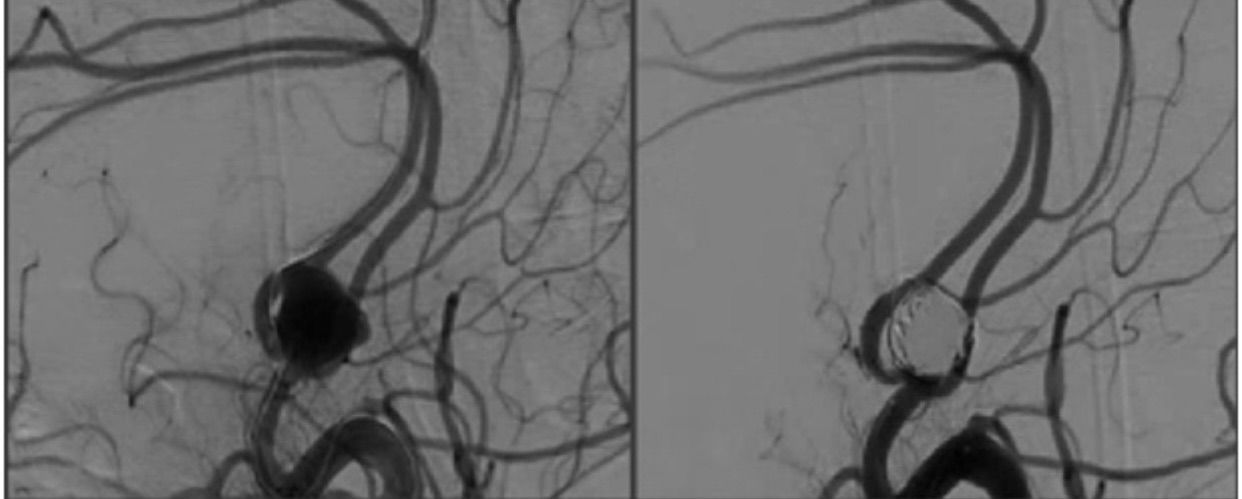

Imaging above depicts an angiogram which captured an anterior communicated artery aneurysm. Neurosurgeons will have various preferences as to whether one should surgically clip or coil the aneurysm. Such treatment options depend on the features of the lesion such as the neck “size“ of the aneurysm. Most neurosurgeons, if chosen craniotomy, will go with a Pterional approach to which is really a lateral sub-frontal skull based exposure (one needs to flatten the sphenoid wing). Then, splitting of the Sylvian Fissure is needed along with a possible gyrus rectus removal (very small portion can be removed which may or may not be necessary).